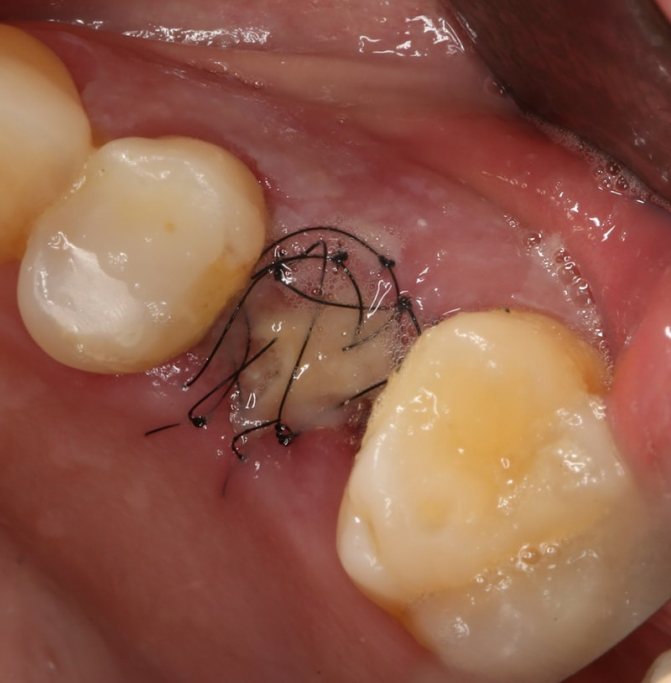

Удаление «восьмерки» – небольшая хирургическая операция. Вследствие того, что зуб мудрости расположен глубоко и имеет несколько корней, врачу приходится делать разрезы на десне. После извлечения зуба ткани ушивают, причем процедура выполняется даже в том случае, если слизистая сильно отекла.

Чаще всего подобная манипуляция проводится при удалении коренного зуба или болезненной «восьмерки». В половине случаев при наличии больших ответвлений и глубоком залегании нерва стоматологу приходится разрезать десну. После этого остается объемная лунка или рана, которая кровоточит и может легко инфицироваться. Накладывая несколько аккуратных стежков, специалист старается предотвратить возможные осложнения:

Первый тип более распространен и характеризуется наложением отдельных, не связанных друг с другом стежков (на фото ниже), и каждый закреплен собственным узлом.

Это сохраняет целостность тканей, даже если один из стежков окажется несостоятельным, отпадет.

Существует непрерывное ушивание. Единой шовной нитью делают все стежки, закрепляя их общим узлом. Это быстрее, но любое повреждение одного стежка может вывести из строя всю конструкцию из нитей.